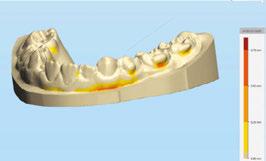

Interproximal recontouring is a crucial component of orthodontic treatment that involves the careful reshaping of tooth surfaces where they touch. This procedure is essential for creating space for teeth movement, improving alignment, and enhancing overall smile esthetics.

Conclusion

Interproximal recontouring is a valuable adjunct to orthodontic treatment that significantly contributes to achieving optimal esthetic outcomes. By carefully selecting and applying appropriate techniques, clinicians can effectively address crowding, diastema, and other dental irregularities, resulting in improved tooth alignment, spacing, and overall facial harmony.